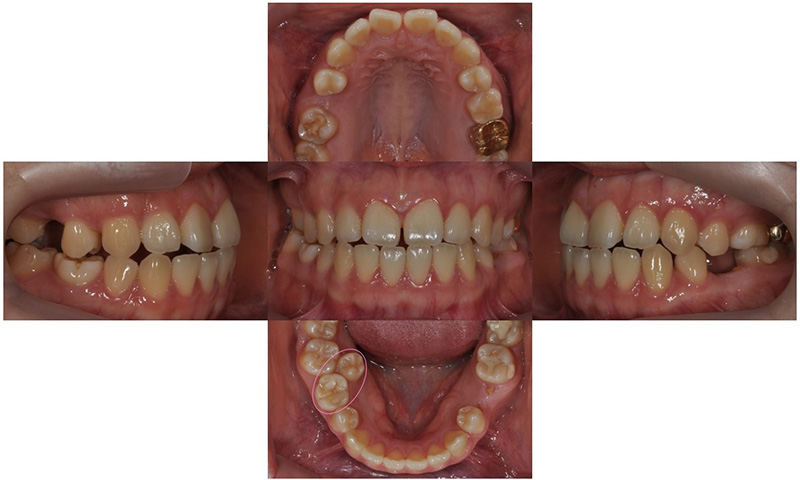

본 환자분은 오른쪽 아래 유구치(유치 어금니)가 남아있고 그 안쪽에 두번째 작은 어금니가 나와 있었습니다. 나머지 세 부위의 두번째 작은 어금니들은 영구치 치배가 없어 유치 어금니로 사용해온 상태였습니다. 왼쪽 아래는 뿌리만 남아있었고, 오른쪽 위에는 유치 어금니가 빠지고 공간이 비어 있었으며, 다행히 왼쪽 위 유치 어금니는 아직 남아 있는 상태였습니다. 아래는 오른쪽의 유치 어금니 및 왼쪽의 비어 있는 어금니 공간이 많이 남아 있고, 상대적으로 위에는 어금니 공간이 부족하여 위아래 앞니도 제대로 물리지 않고 있었습니다.

오른쪽 아래 치아들과 같이 치아가 겹쳐져 있게 되면, 교합이 맞지 않을 뿐만 아니라 그 사이 부위의 구강위생관리가 제대로 이루어질 수 없기 때문에 충치가 생길 확률이 높으며, 잇몸도 안좋아질 수 있습니다.

환자의 안모상 안쪽에 위치한 치아를 뽑아서 남아있는 공간들을 모두 닫게 되면 입이 너무 들어가보일 수가 있었기 때문에, 오른쪽 아래 유치 어금니를 발치하여 안쪽에 이소맹출한 작은 어금니를 재위치 시키고, 나머지 비어있는 공간에는 임플란트를 식립하기로 했습니다.